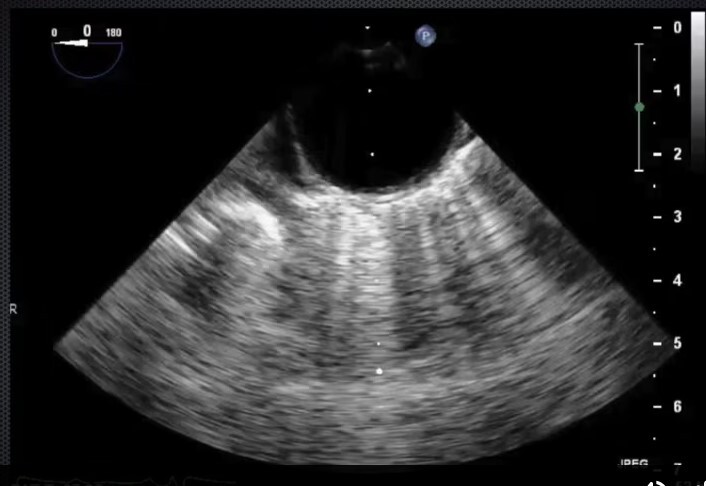

Trans-gastric mid-papillary short axis view - start at ME 4CH view at 0 on the multiplane, advance probe to stomach and then anteflex. Manipulate probe depth until you can see posteromedial and anterolateral papillary muscles. See right and left ventricles. Good for regional wall movement abnormalities. Good for volume assessment.